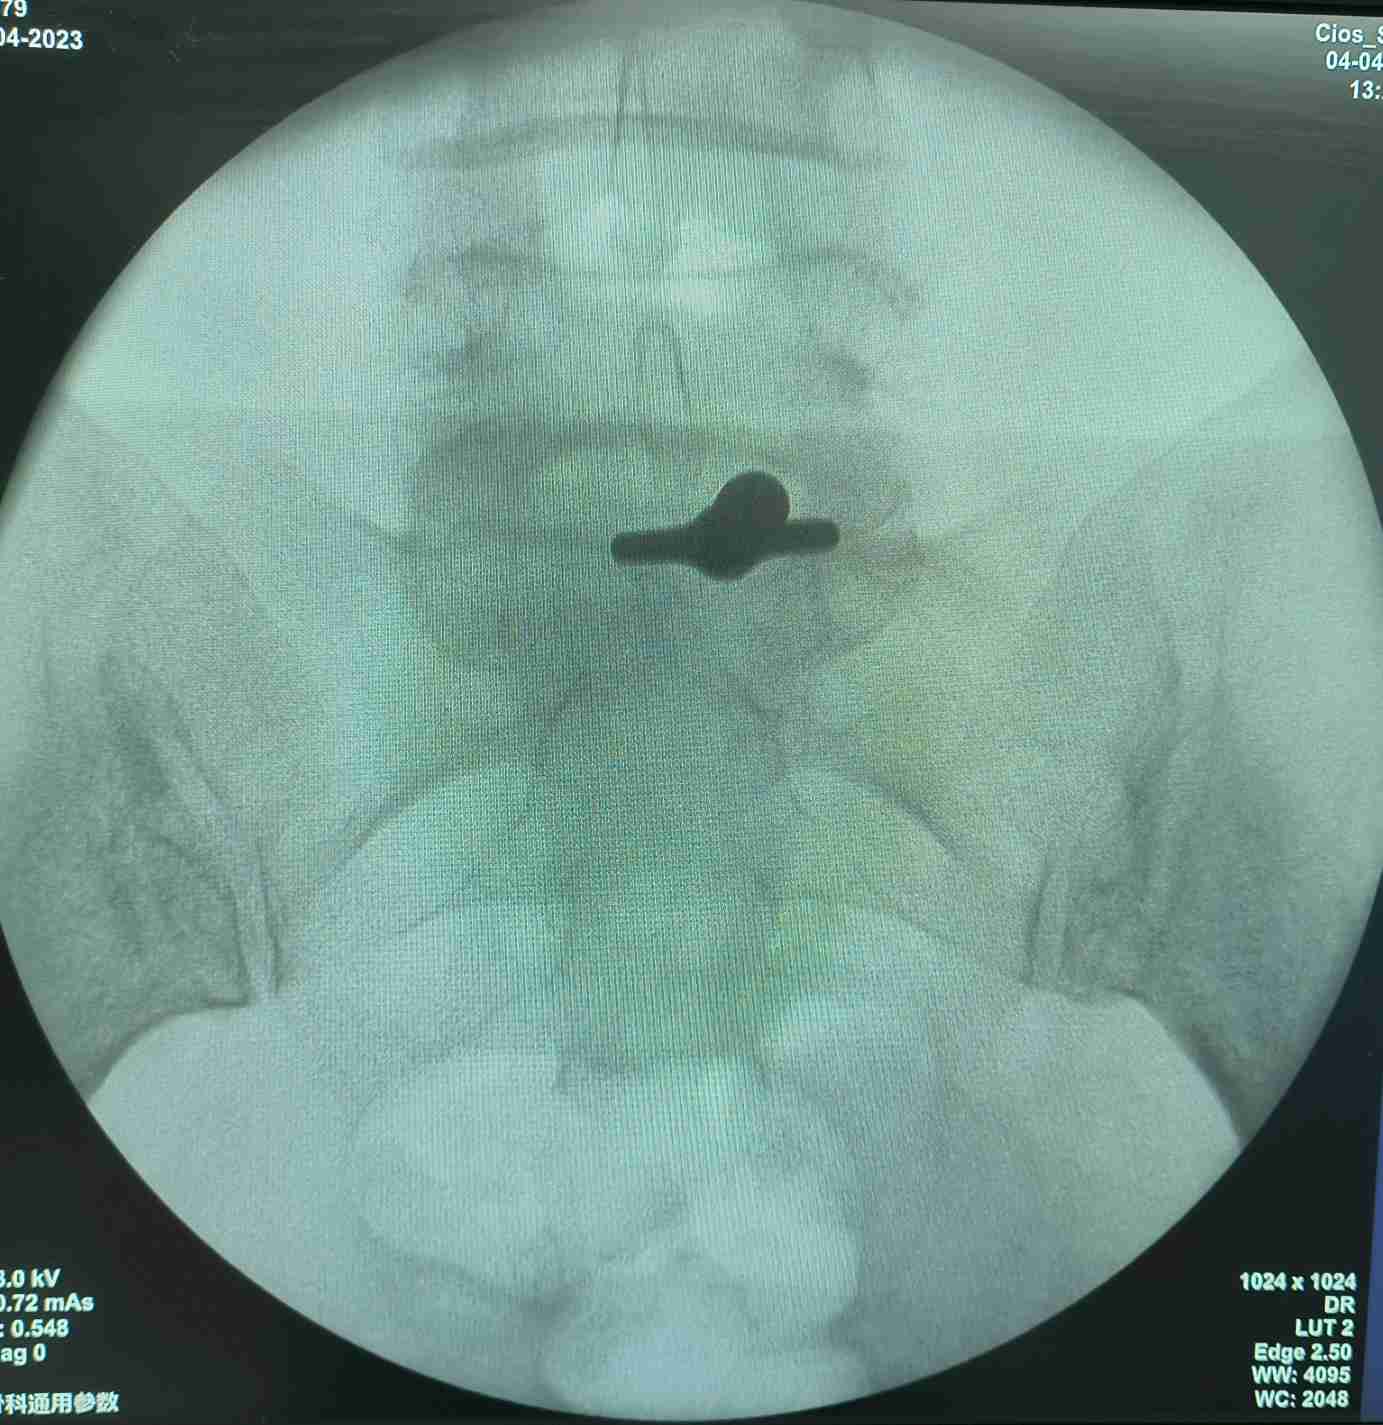

一个0.7cm大小的切口,下一个内镜进去,半个小时,全程无痛,就解决了神经受压,术中即感疼痛消失!

看着椎管内自由的神经根,心情是愉悦的,患者的心情更加愉悦,因为没有了那种钻心的疼痛!